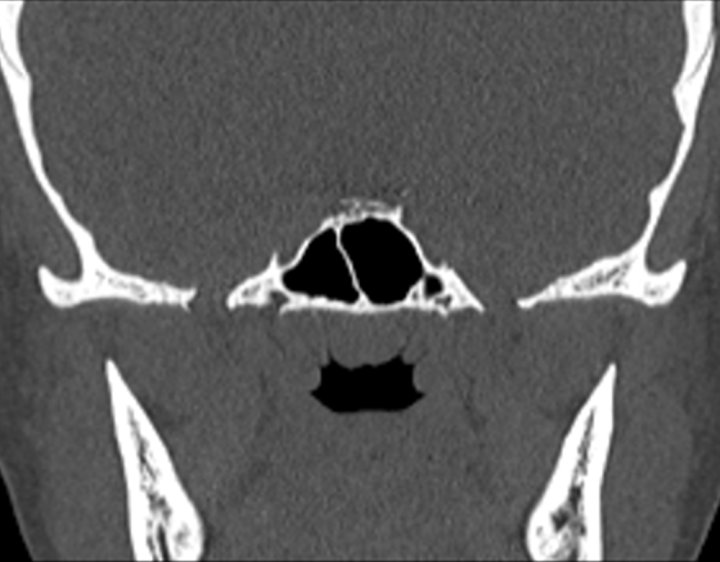

Click any image for labels.